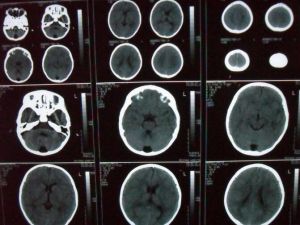

枕大池(又稱小腦延髓池),位於顱後窩的後下部,小腦下面、延髓背側面與枕鱗下部三者之間。 向前經小腦溪通第四腦室;向前外經延髓側面通延髓池。三維斷面均可顯示。